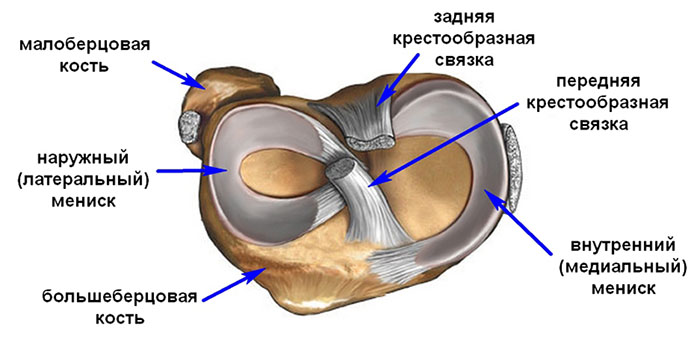

Анатомические изображения менисков и коленного сустава

Раздел: Иллюстрированные советы